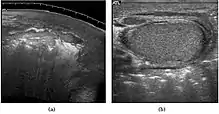

Epididymo-orchitis in a 77-year-old man. (a) Transverse sonography shows enlargement of the epididymis with hypoechogenicity noted over the testis and epididymis associated with scrotal wall thickening. (b) Color Doppler sonography showed hyperemic change of the testis and epididymis, presenting as an “inferno” vascular flow pattern.

Epididymitis and epididymo-orchitis are common causes of acute scrotal pain in adolescent boys and adults. At physical examination, they usually are palpable as tender and enlarged structures. Clinically, this disease can be differentiated from torsion of the spermatic cord by elevation of the testes above the pubic symphysis. If scrotal pain decreases, it is more likely to be due to epidiymitis rather than torsion (Prehn's sign). Most cases of epididymitis are secondary to sexually transmitted disease or retrograde bacteria infection from the urinary bladder.[4] The infection usually begins in the epididymal tail and spreads to the epididymal body and head. Approximately 20% to 40% of cases are associated with orchitis due to direct spread of infection into the testis.

At ultrasound, the findings of acute epididymitis include an enlarged hypoechoic or hyperechoic (presumably secondary to hemorrhage) epididymis [Fig. 20a]. Other signs of inflammation such as increased vascularity, reactive hydrocele, pyocele and scrotal wall thickening may also be present. Testicular involvement is confirmed by the presence of testicular enlargement and an inhomogeneous echotexture. Hypervascularity on color Doppler images [Fig. 20b] is a well-established diagnostic criterion and may be the only imaging finding of epididymo-orchitis in some men.